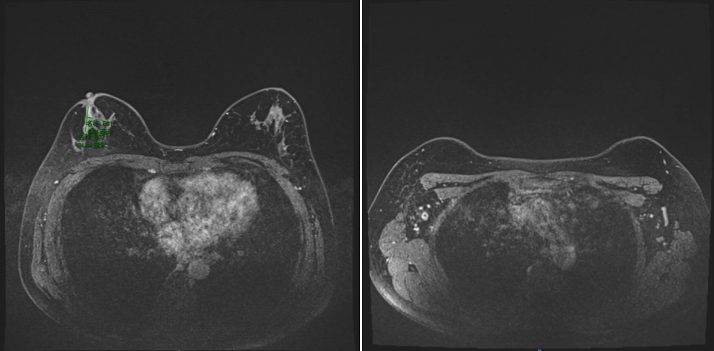

2021-12-01,乳腺MR:右乳外上象限腺体内(约9-12点钟方向,前中带区)见一异常信号肿块影,大小约3.9×2.7cm,符合乳腺癌表现(BI-RADS 6类),侵及邻近皮肤及乳头。右侧腋窝数个增大及稍大淋巴结,较大者大小约为2.1×1.3cm,考虑转移。

图2.乳腺MR(2021-12-01)